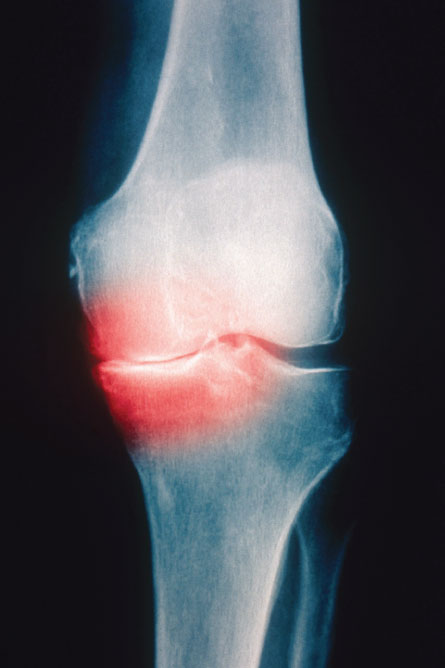

Feature Health & Medicine Cartilage Creation New joint tissue could keep people moving, reducing need for knee or hip replacements By Nathan Seppa July 27, 2012 at 11:04 am - More than 2 years ago Share this:Share Share via email (Opens in new window) Email Click to share on Facebook (Opens in new window) Facebook Click to share on Reddit (Opens in new window) Reddit Click to share on X (Opens in new window) X Click to print (Opens in new window) Print Cartilage, the shock absorber of the body, has been bearing the brunt of a modern lifestyle. Glassy, resilient bone-capping cartilage has long eluded tissue engineers trying to grow it in the lab. Biophoto Assoc./Getty Images When cartilage wears away, bone rubs on bone (as shown in this color-enhanced X-ray of a 76-year-old man’s knee).